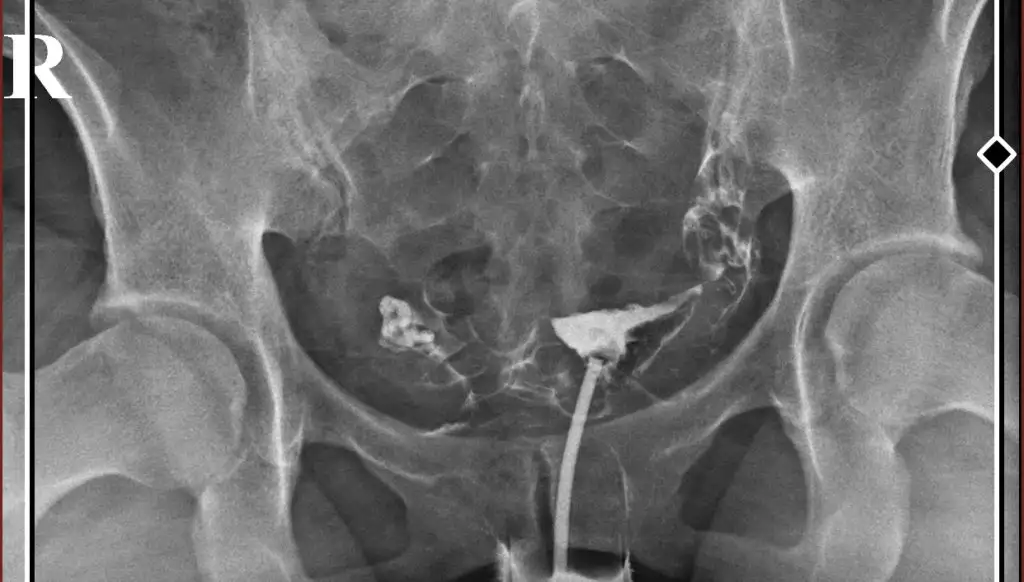

Kızlar dün rahim filmi çekindim doktor sol tüpün kapalıydı açtık dedi ana sanki açılmamış gibi bi bakar mısınız

S Sareali36 Kullanıcı üyeliğini pasifleştirmiştir. Üyelik İptali Kayıtlı Üye 29 Aralık 2023 555 191 18 28 Temmuz 2024 Konu Sahibi Konu Sahibi aysssseee #2 aysssseee .!.: Kızlar dün rahim filmi çekindim doktor sol tüpün kapalıydı açtık dedi ana sanki açılmamış gibi bi bakar mısınız Eki Görüntüle 3457743 Genişletmek için tıkla... Bana da öyle geldi sanki kontrast sıvı dağılmamış gibi tekrar edin veya bi sorun bence

aysssseee .!.: Kızlar dün rahim filmi çekindim doktor sol tüpün kapalıydı açtık dedi ana sanki açılmamış gibi bi bakar mısınız Eki Görüntüle 3457743 Genişletmek için tıkla... Bana da öyle geldi sanki kontrast sıvı dağılmamış gibi tekrar edin veya bi sorun bence